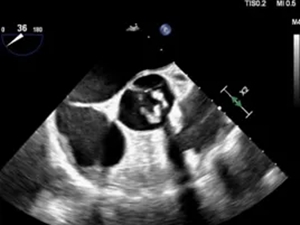

经食道超声主动脉瓣

二瓣畸形